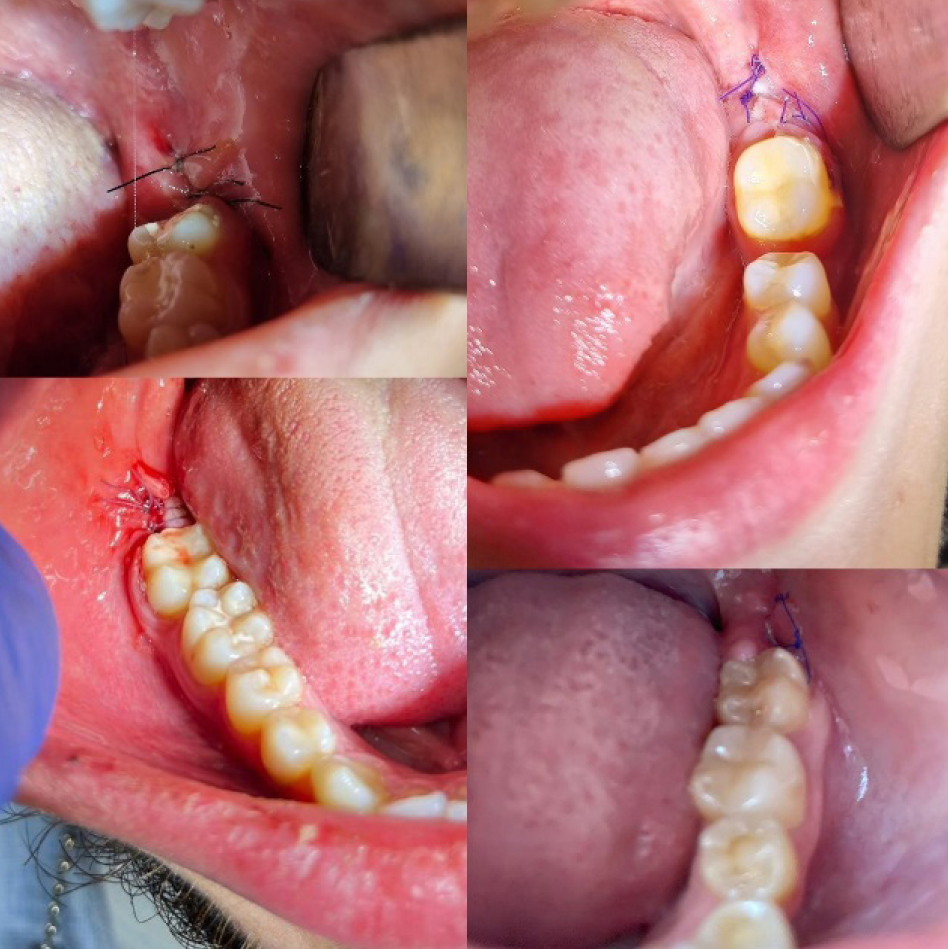

Рис. 1. Конусно-лучевая компьютерная томография

Дополнительные методы обследования включали в себя проведение конусно-лучевой компьютерной томографии (рис. 1), измерение расстояния между центральными резцами нижней и верхней челюсти (рис. 2), для оценки функционального состояния жевательных мышц было проведено электромиографическое исследование.